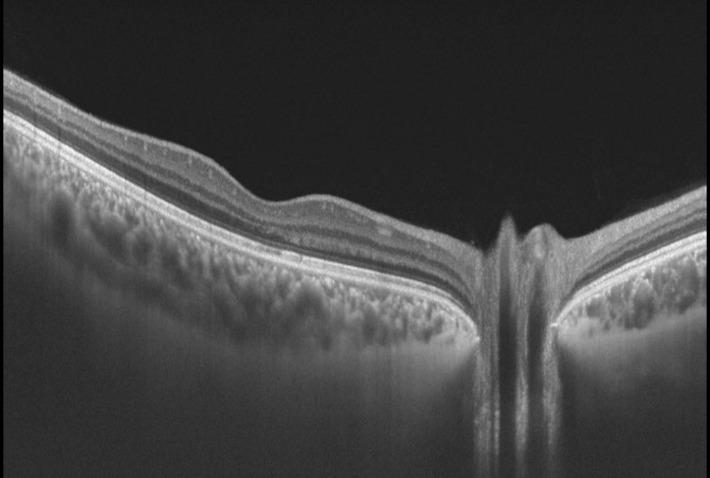

תמונת OCT תקינה של מרכז הרשתית, המקולה, עם שקע מרכזי תקין